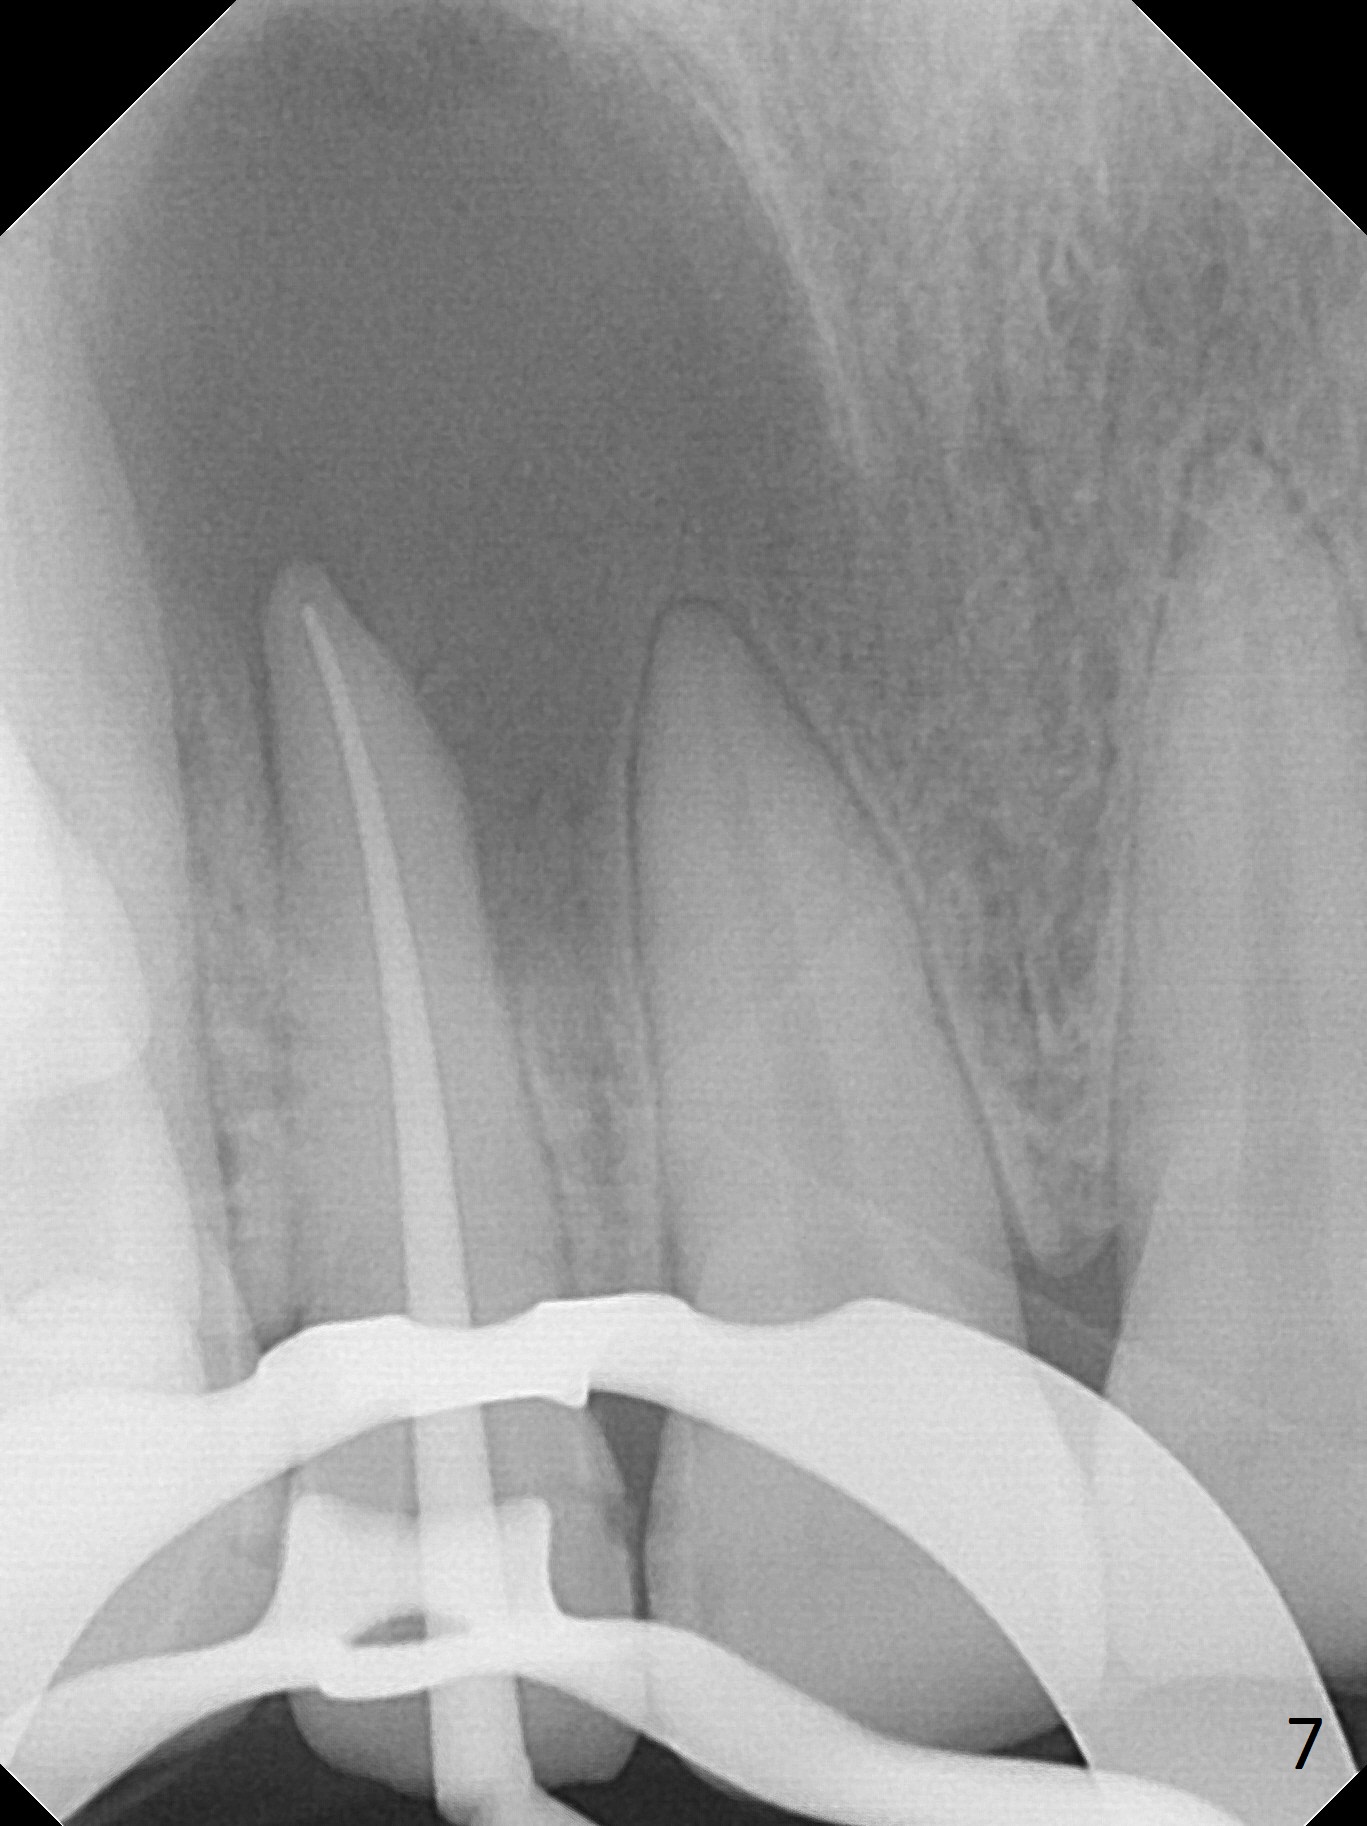

When this patient returns with improvement of symptoms, RCT will be finished. In fact the swelling relapses a month later (Fig.6). After discussion of possible cyst enucleation and increase in debridement from 30/.04 to 40/.06, a master cone of 40/.06 is inserted (Fig.7) and RCT is finished (Fig.8). Although the patient reports relapse of swelling, the palate looks normal and bone density increases 7 months postop (Fig.9). For 14 implant placement, CT is taken 2 years 1 month post RCT (Fig.10,11). Radiolucency is confined to the apex of the tooth #7 (white *). The labial concavities mesial and distal to the left lateral incisor makes radiolucencies (bone loss) look more radiolucent, creating globumaxillary cyst image. The globumaxillary cyst is a terminology for its shape. It does not mean congenital in nature. The treatment is dependent upon vitality test of the involved teeth.